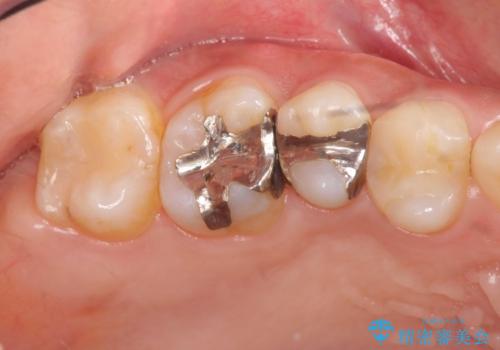

- 歯が痛み、改善を求めて来院されました。

歯の神経の治療(根管治療)が必要であることをご説明し、同時に隣在する銀歯の除去も希望されたので同時に治療を行っていきます.